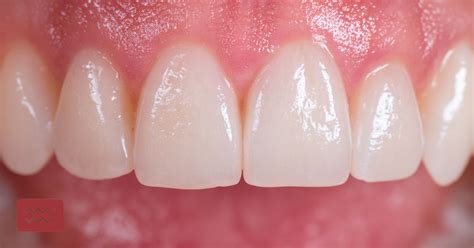

Para detener el sangrado de encías, asegúrate de cepillarte los dientes y utilizar hilo dental, y de visitar a tu higienista dental para hacer una limpieza de dientes al menos dos veces al año. Sigue una buena rutina de cuidado en casa que incluye hilo dental diario, cepillado con una pasta dentífrica antibacteriana dos veces al día durante 2 minutos y utilizar un enjuague antibacteriano.

Es fundamental educar a los pacientes sobre técnicas adecuadas de cepillado y uso del hilo dental. Para evitar la acumulación de sarro y tener una buena higiene bucal, los dentistas recomendamos siempre realizar un correcto cepillado (evitar cepillos de cerdas fuertes o cepillados agresivos) mínimo dos veces al día y utilizar hilo dental o dispositivos específicos para llegar a las zonas más difíciles.

- Uso correcto del cepillo de dientes: Una de las maneras más sencillas para evitar el sangrado es utilizar de forma correcta el cepillo de dientes. Trata de cepillarte durante más de 2 minutos para obtener un resultado óptimo.

- Tipo de cepillo dental: El cepillado puede realizarse manualmente con un cepillo de dureza media con una técnica de cepillado correcta o mediante un cepillo eléctrico que simula el movimiento circular que haríamos manualmente, pero con control, de tal manera que es menos probable que dañemos nuestras encías. Utilizar un cepillo de cerdas suaves es crucial para no causar daño en los tejidos gingivales. Como alternativa, utiliza cepillos más suaves que sean delicados con tus encías sensibles o inflamadas.

- Pasta de dientes adecuada: Lo mejor es utilizar un dentífrico que ayude a eliminar las bacterias que causan la inflamación. Por ejemplo, hay dentífricos antibacterianos con clorhexidina que puedes usar además de un colutorio o gel. La pasta de dientes también debe ser suave para proteger las encías ya irritadas.